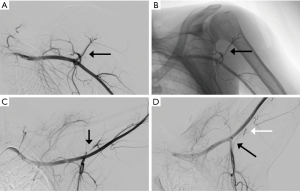

MRI has traditionally been used to demonstrate fatty atrophy of the teres minor or deltoid muscles (4,10). Typical findings on T1 weighted sequences include atrophy and fatty infiltration (Figure 2) but space occupying lesions such as neuromas, tumors, hypertrophied adjacent muscles or vascular aneurysms may be seen. T2-weighted sequences, typically fast spin-echo with fat suppression are used to detect abnormalities such as paralabral cysts. Diffuse increased T2 signal in the teres minor may suggest neurogenic edema consistent with QSS. MR angiography (MRA) can be used similarly to CTA to identify vascular abnormalities in the PCHA and distally in the arm. MRI has also been described as a possible modality to evaluate for axillary nerve compression, particularly at high fields such as 3 Tesla (11). Contributing shoulder pathologies such as rotator cuff or labral pathology can be identified by MRI or MR arthrography. In the case of MR arthrography, contrast is injected directly in the shoulder joint with fluoroscopic guidance followed by MR imaging, making it more sensitive for tears and paralabral pathology. Cahill and Palmer suggested the use of angiography as a diagnostic tool (1). Fluoroscopic and digital subtraction angiographic images are obtained after intra-arterial contrast injection into the subclavian or axillary artery. Images are obtained in both the neutral and abducted/externally rotated positions. The PCHA may be attenuated or entirely occluded with findings more pronounced in the abducted position (Figure 3). For non-acute patients suspected of QSS, diagnostic angiography could also identify chronic arterial changes such as aneurysm formation, dissection or partially occlusive thrombus allowing for intervention prior to the appearance of emboli or acute occlusion. In the acute stages, peripheral ischemia from emboli originating in the PCHA may be present with angiography showing complete arterial occlusion or aneurysm formation in the PCHA. In these patients, angiography is not only diagnostic, but allows for immediate intervention such as with thrombolysis.

In patients who presently with acute symptoms such as discoloration, pale or cool hand or digits, absent or diminished Doppler signals at the wrist, anticoagulation should be initiated and endovascular intervention may be performed. An arch angiogram with upper extremity runoff followed by catheter directed thrombolysis may be performed. After a period of up to 48 hours, thrombolysis may then be followed with therapeutic anticoagulation for several months (6).